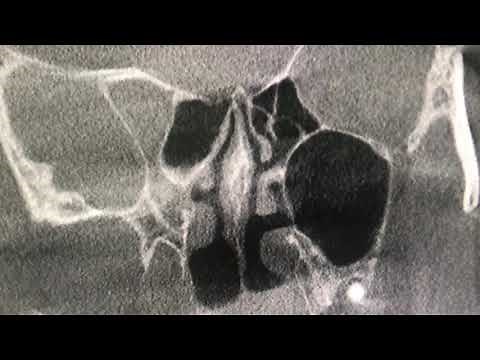

We analyze a cone beam CT scan, highlighting a deviated septum, large turbinates, and narrow pharyngeal airway. We discuss skeletal intermolar distance, potential breathing

Dr David McIntosh. . We analyze a cone beam CT scan, highlighting a deviated septum, large turbinates, and narrow pharyngeal airway. We discuss skeletal intermolar distance, potential breathing issues, and possible solutions like ENT referral and orthodontic treatment. #ConeBeamCT #DeviatedSeptum #AirwayAnalysis #Orthodontics #SleepApnea #ENT # ...

Deviated Nasal Septum explained with Cone Beam CT scan